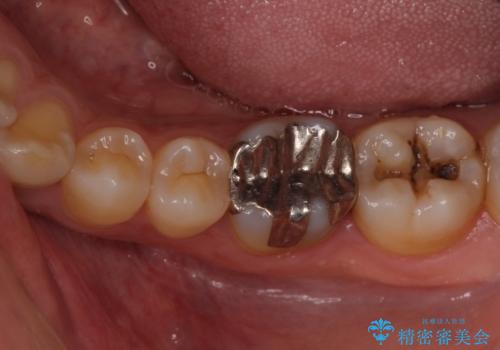

それよりも奥から2番目の歯のほうが、適合不良の銀のつめものが入っており、大きな虫歯が疑われました。

虫歯の大きさや形を加味して、1番奥を保険治療、奥から2番目をセラミック治療で行うことになりました。

ご来院当初、患者様は1番奥歯のセラミック治療をご希望されてました。しかし、しっかり診査をして1本手前の歯を治療した方が良いとご提案させて頂きました。

また、奥歯が虫歯になりやすい原因として夜間の歯ぎしりで、歯に小さいヒビが入っている疑いがありました。就寝時マウスピースを使用して予防して頂くこともご提案し、患者様には大変満足して頂きました。